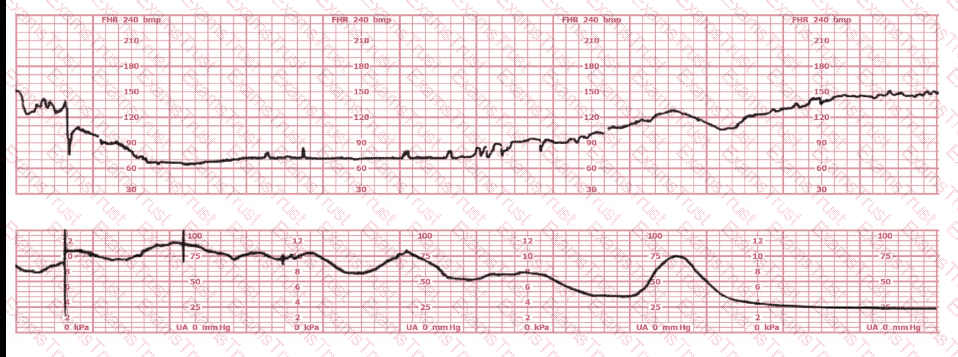

This tracing would be categorized as a

This tracing is consistent with:

The most probable underlying fetal physiologic cause for this tracing would be:

This patient received an epidural 15 minutes prior to the tracing shown. The next course of action is to: